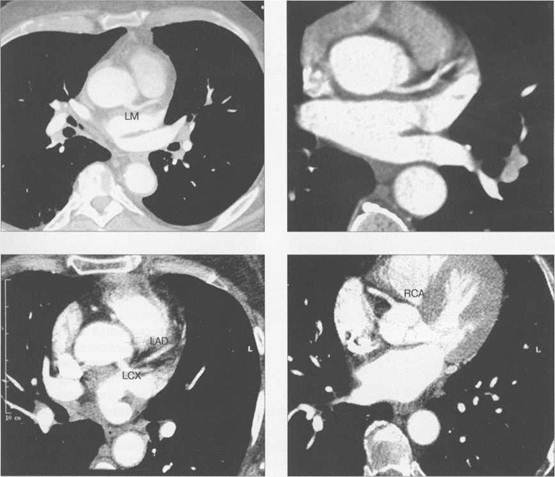

МСКТ в условиях внутривенного болюсного контрастирования позволяет визуализировать коронарные артерии (МСКТ-коронарография). Анализ состояния коронарных артерий вы­полняется сначала на аксиальных срезах (рис. 9.35). В постпроцессинговой обработке изоб­ражений используются различные виды реконструкций: многоплоскостные реформации (MPR), проекция максимальной интенсивности (MIP), трехмерные (VRT) (рис. 9.36).

Рис. 9.35. МСКТ-коронарограммы. Поперечные срезы.

Здесь и на рис. 9.36:

LM — ствол левой коронарной артерии, LAD — левая передняя нисходящая артерия, LCX — левая оги­бающая артерия, RCA — правая коронарная артерия.